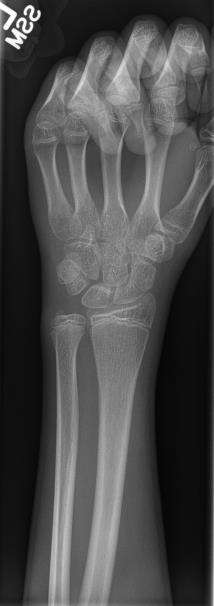

The creation of images by exposing an object to X-rays or other high-energy forms of electromagnetic radiation and capturing the resulting remnant beam (or "shadow") as a latent image is known as "projection radiography." The "shadow" may be converted to light using a fluorescent screen, which is then captured on photographic film, it may be captured by a phosphor screen to be "read" later by a laser (CR), or it may directly activate a matrix of solid-state detectors (DR—similar to a very large version of a CCD in a digital camera). Bone and some organs (such as lungs) especially lend themselves to projection radiography. It is a relatively low-cost investigation with a high diagnostic yield. The difference between soft and hard body parts stems mostly from the fact that carbon has a very low X-ray cross section compared to calcium.

- Hard tissues such as bone require a relatively high energy photon source, and typically a tungsten anode is used with a high voltage (50-150 kVp) on a 3-phase or high-frequency machine to generate bremsstrahlung or braking radiation. Bony tissue and metals are denser than the surrounding tissue, and thus by absorbing more of the X-ray photons they prevent the film from getting exposed as much.[1] Wherever dense tissue absorbs or stops the X-rays, the resulting X-ray film is unexposed, and appears translucent blue, whereas the black parts of the film represent lower-density tissues such as fat, skin, and internal organs, which could not stop the X-rays. This is usually used to see bony fractures, foreign objects (such as ingested coins), and used for finding bony pathology such as osteoarthritis, infection (osteomyelitis), cancer (osteosarcoma), as well as growth studies (leg length, achondroplasia, scoliosis, etc.).

- Soft tissues are seen with the same machine as for hard tissues, but a "softer" or less-penetrating X-ray beam is used. Tissues commonly imaged include the lungs and heart shadow in a chest X-ray, the air pattern of the bowel in abdominal X-rays, the soft tissues of the neck, the orbits by a skull X-ray before an MRI to check for radiopaque foreign bodies (especially metal), and of course the soft tissue shadows in X-rays of bony injuries are looked at by the radiologist for signs of hidden trauma (for example, the famous "fat pad" sign on a fractured elbow).